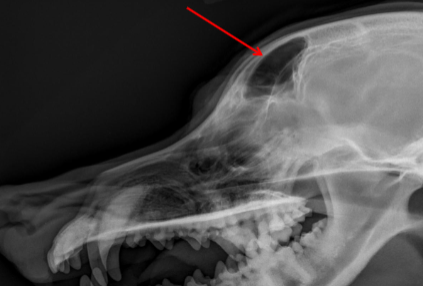

ID Radiographic View

Lateral

Maxilla

ID

Zygomatic Bone

Orbital Margin

Coronoid Process of Mandible